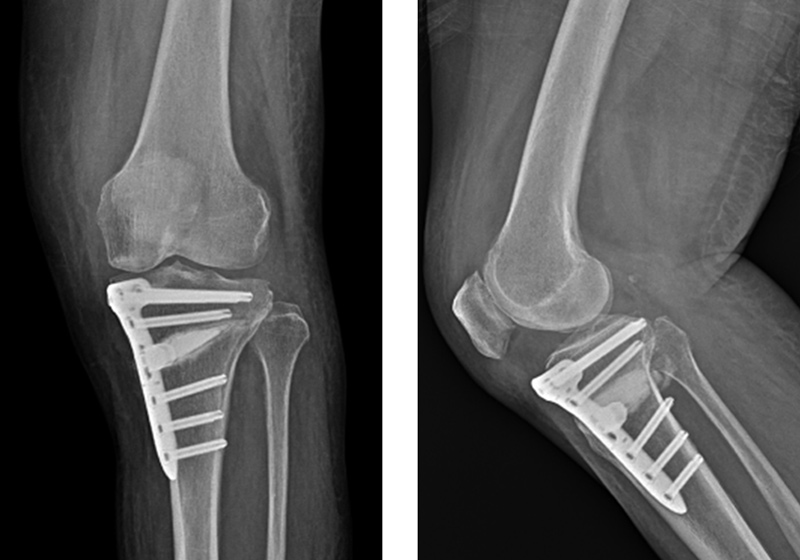

O자로 휜 다리는 방치할 경우 무릎 관절염으로 이어질 우려가 크고 장기간 지속되면 골반과 허리에도 무리가 되어 척추 질환을 유발하기도 합니다. 고관절 중심에서 발목 중심을 이은 선을 하지의 축이라고 하는데 보행시 체중이 가해지는 선입니다. 축이 무릎의 중앙이 아닌 안쪽을 지나게 되고 무릎 안쪽이 체중 부하를 많이 받아 관절연골이 손상되고 관절 간 간격도 좁아지면서 퇴행성 관절염이 발생하기 쉽습니다.

하지의 축을 내측에서 외측으로 옮겨주어 손상되지 않은 건강한 바깥쪽 연골에 체중을 더 부과시켜 관절염을 치료하는 ‘경골근위부절골술’이 효과적입니다. 이 수술은 흔히 ‘휜다리 교정술’이라고도 부르는데 휜 다리를 교정함으로써 관절염을 치료하는 수술법으로 주로 60세 미만의 활동적인 환자에게 적합하며 인공관절없이도 관절염의 치료가 가능하며 다리 모양 또한 일자로 바르게 바뀌어 환자들의 만족도가 큰 치료법입니다.